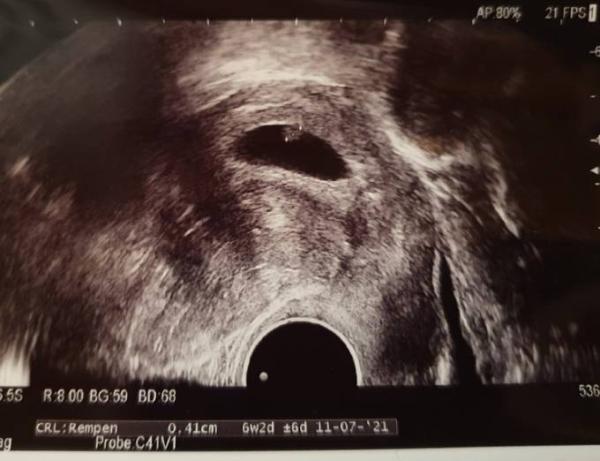

Hallo Mädels Ich hatte ja an Dienstagmorgen meinen FA-Termin, kam aber bisher nicht dazu, mal zu berichten Vom US her sieht alles super aus, das Herzchen schlägt Laut US-Gerät wäre ich zwei Tage zurückdatiert, aber meine Ärztin meint, das ist ja immer noch fast zeitgerecht und tag-genau und kann bei so einem kleinen Würmchen auch am Messen liegen. Nächster Termin ist am 15.12., da wird das Ausmessen dann schon besser möglich sein Heute Morgen hat dann die Praxis nochmal angerufen wegen der Blutwerte. Muss nun Vitamin D nehmen, da mein Wert zu niedrig ist und der Schilddrüsenwert ist nicht ganz okay (habe das mittesten lassen, da ich es sowieso mal machen lassen wolltr da es in der Familie liegt). Habe direkt nächste Woche (das ging echt schnell. Die FA-Praxis meinte nur, ich solle von der Schwangerschaft erzählen, dann bekäme man recht zeitnah einen Termin ) einen Termin beim Spezialisten und dann wird weitergeschaut. (Das würde auch evtl. erklären, warum sich vor der Schwangerschaft trotz Sport und Ernährung nichts am Gewicht getan hat ) Aber im Großen und Ganzen bin ich sehr erleichtert, dass alles gut ist

Bild zu FA-Termin vorgestern - Forum für Juli - Mamis